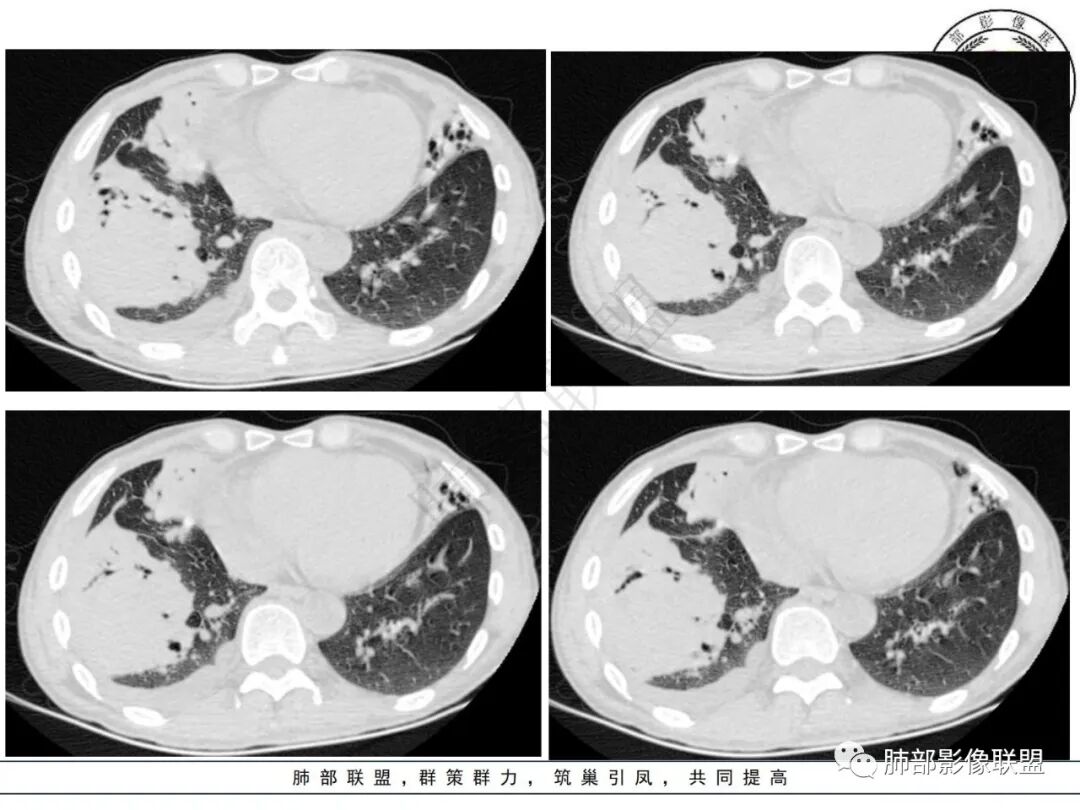

衡妈:有没有可能吸入了啥引起的感染,比如汽油。两肺门周围较大实变及囊腔型病灶,右侧实变可见扩张的支气管,夹杂磨玻璃影;左侧囊壁略厚,囊腔不规则,内多分隔,近端支气管感觉有堵塞。其余两肺散在小空洞性病灶。纵隔可见明显肿大淋巴结。先考虑感染性病变,鉴别肿瘤性病变,淋巴瘤。

丽:双肺多发结节及片状实变密度影,实变内可见支气管穿行,走形僵直,部分见多发囊腔,内可见分隔,壁厚薄不均,支气管管壁略增厚,右侧胸腔积液,考虑恶性,淋巴瘤,鉴别囊腔型腺癌。

小兜:男,53岁,气促入院。CT示双肺多发实变影,右肺为著,左肺可见较大分隔囊腔,壁不均匀增厚,右肺可见多发支气管扩张伴周围实变影,右肺较大实变可见支气管截断,内可见支气管充气征,纵隔多发肿大淋巴结,综上所述考虑恶性,淋巴瘤可能。

宇宙:右肺肿块,边缘膨隆,其内支气管扩张、扭曲,少许坏死,上叶前段支气管阻塞,左肺囊腔,壁薄厚不均,其内见分隔,两肺另见多发结节,纵膈淋巴结肿大,右侧胸水,考虑腺癌,鉴别淋巴瘤。

1.病例特点:中年男性,气促,中长病程。贫血明显,无发热。实验室轻度异常(C反应蛋白升高)。双肺多发结节、片状影,边界可分辨,多见支气管穿行,走形僵直。左肺上叶较大囊腔,腔内分隔明显,壁薄不均,可见结节样增厚,相邻肺组织膨胀不全。右肺上叶块影巨大,多支气管穿行,前段支气管闭塞,后段支气管扩张。余支气管管壁前段增厚。右上纵隔多发肿大淋巴结。右侧胸腔积液。